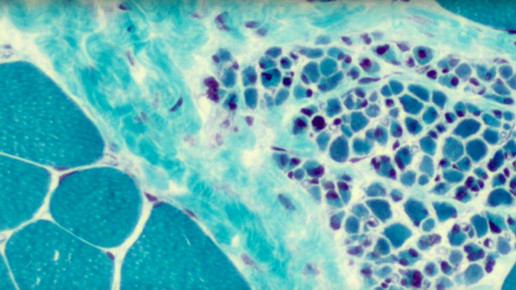

ALS ist eine nicht heilbare degenerative Erkrankung des motorischen Nervensystems, es kommt zum Zelluntergang der motorischen Zellen im Gehirn und Rückenmark. Das Haupterkrankungsalter liegt zwischen 50 und 70 Jahren, dabei erkranken Männer häufiger als Frauen. Etwa zwei bis acht Menschen von 100.000 leiden an ALS.

Im Laufe der Erkrankung treten schmerzlose Lähmungen mit einer Erhöhung der Muskelspannung auf, unwillkürliche Zuckungen können deutlich sichtbar sein. Es kommt zu Muskelkrämpfen und Muskelversteifungen bis hin zu allgemeiner Kraftlosigkeit und Muskelschwund. Betroffen von der Erkrankung können alle Muskelpartien sein, ausgenommen Augen-, Herz- und Schließmuskel.